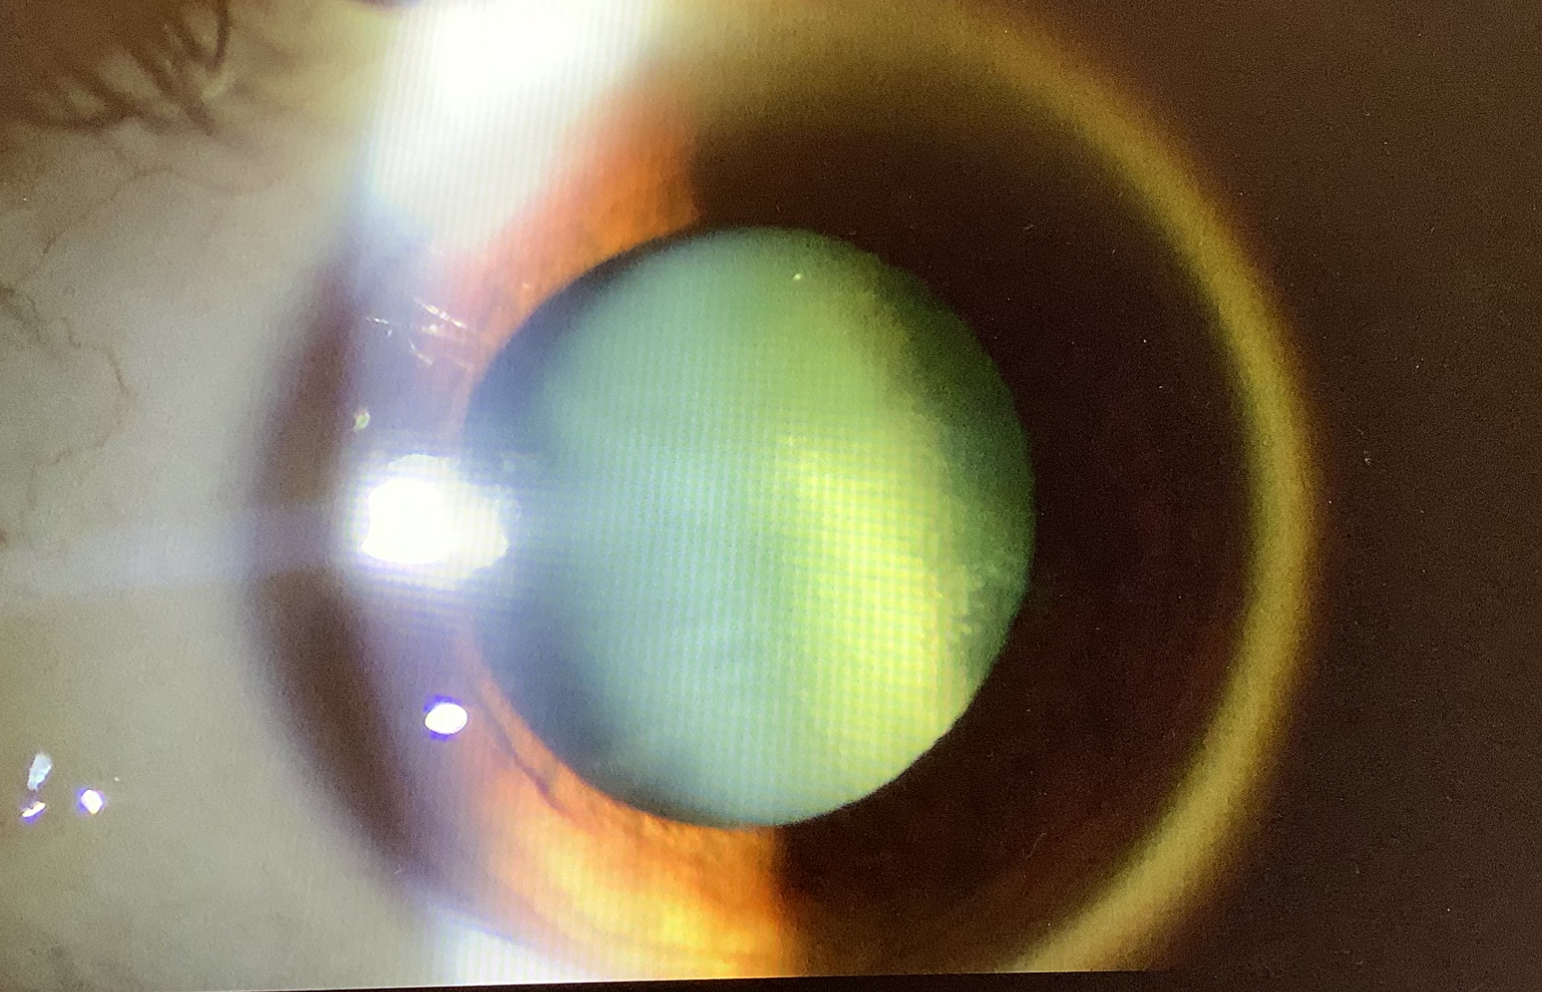

今日、白内障の手術を予定していた40代半ばの男性の方は、先月、糖尿病網膜症の硝子体出血で水晶体温存の硝子体手術を行った方で、その手術の後に急速に白内障が進行してしまっていました。硝子体手術の時に、器具が水晶体に触れたせいで白内障が出ていましたが、進み具合が急だったので、水晶体の袋(水晶体嚢)の損傷の可能性もあるかと思いながら手術を始めましたが、超音波で水晶体を削り始めるとすぐに水晶体が硝子体側に落ち込み、やはり前回の硝子体手術の時に、水晶体嚢を傷つけてしまっていたようで、そのまま眼底に落下してしまいました。